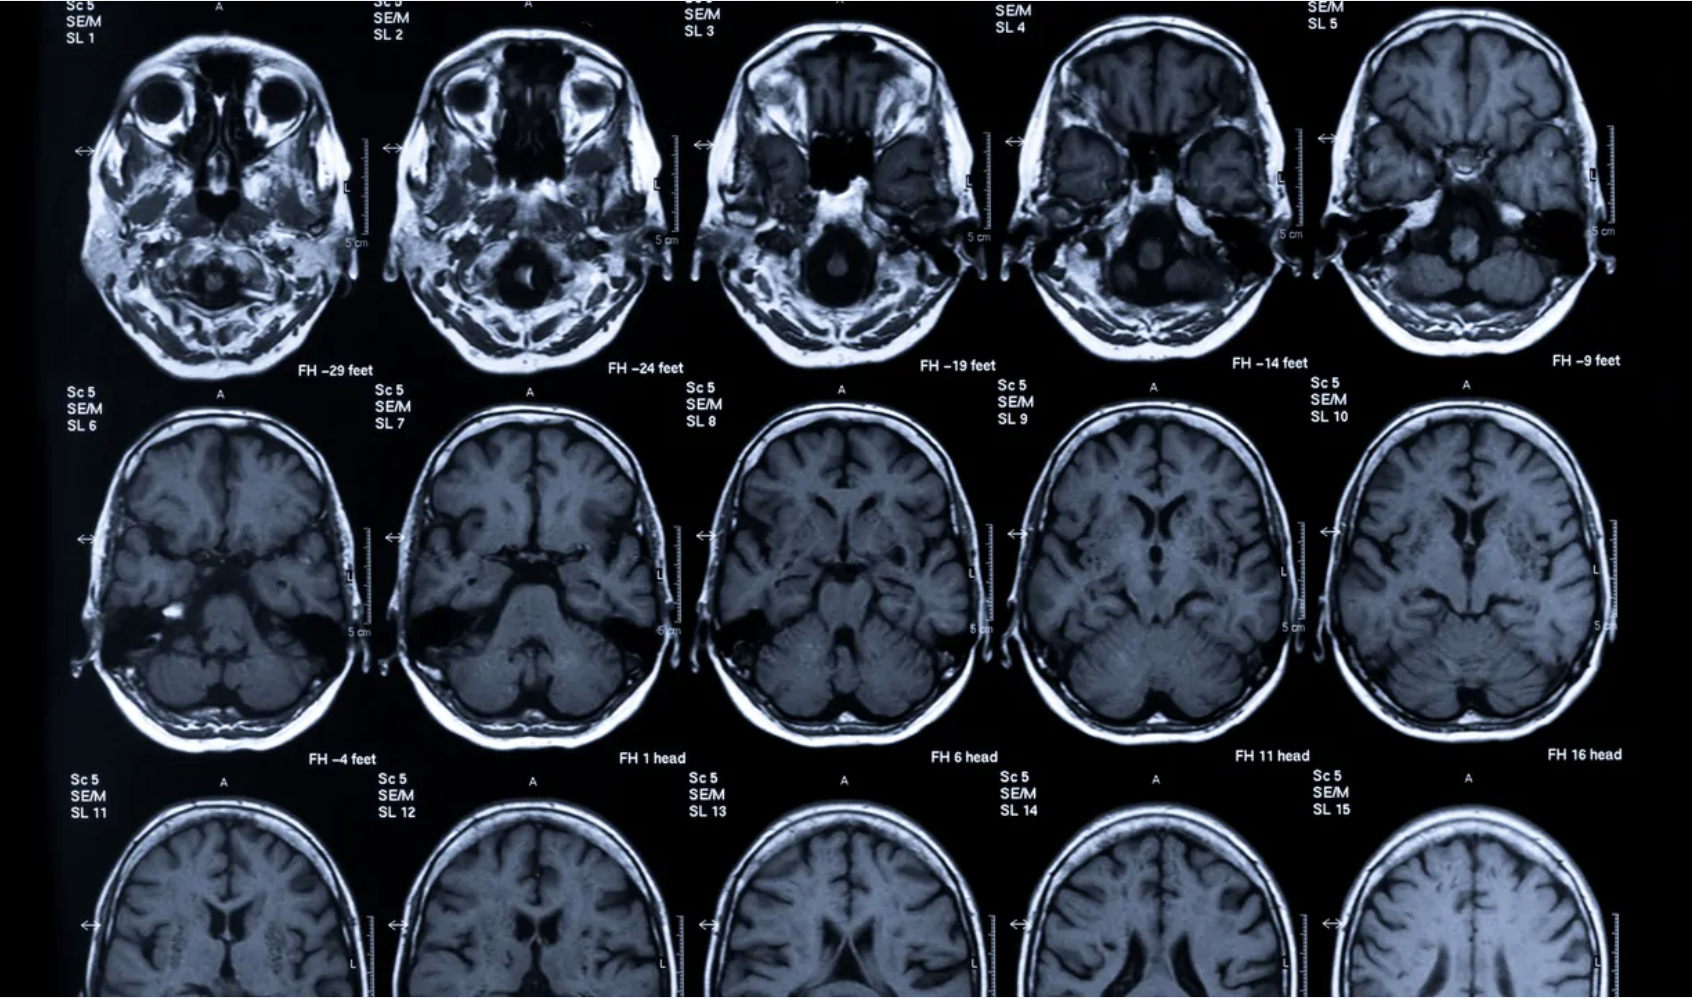

Brain Activity

Objective neural measures, including neuroimaging and brain markers, to provide insight into functional brain states.

Psychiatric assessments rely heavily on subjective clinician-rated scales (e.g., HAM-D, PANSS) or patient-reported outcomes, introducing variability and bias. Neuroimaging-based biomarkers offer objective, quantifiable endpoints that can reduce this noise and improve signal detection.

Our platform directly addresses these pain points and is designed to reduce trial failure risk by offering neuroimaging-based biomarkers that stratify patients and predict individual placebo or treatment response. Our biomarkers are grounded in robust neuroscience, clinically interpretable, and regulator-ready.

Our proprietary platform leverages machine learning to detect predictive signatures of treatment and placebo response in CNS disorders. We integrate structural and functional imaging with rigorous clinical data to deliver: